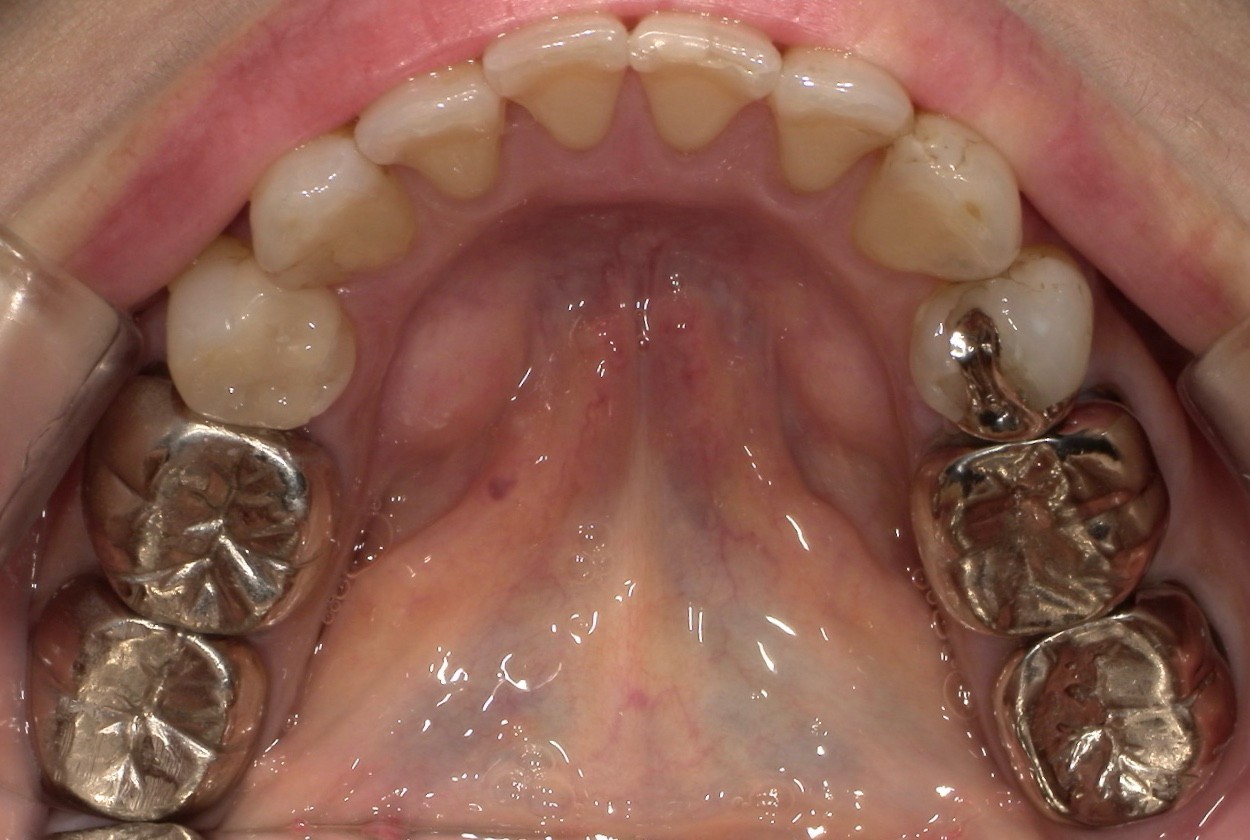

CASE 01

Before

After

施術内容下の銀歯が目立つので、白くしたいとのご希望。奥歯(左右第1大臼歯)の銀歯のかぶせ物をセラミックのかぶせ物(クラウン)に交換。

治療期間1か月

リスク・副作用セラミックは陶器の一種であるため、強い衝撃によって割れたり欠けたりする可能性があります。特に、噛む力が強くかかる奥歯は、前歯に比べて破損のリスクが高まります。

費用198,000円(税込み)

※表示金額は全て税込みです。